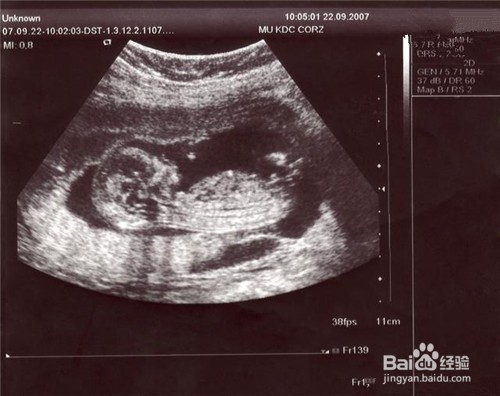

1、宝宝B超扫描照片在怀孕期间,妈妈会做很多次B超,至少还会做一鸱远忡绑次高清晰4维彩超,更清晰的看到孩子的样貌。建议妈妈们把这些B超照片按照顺又挨喁钒序给孩子好好的保存起来,这份资料太珍贵了,等他长大了再回头细细看,就能有别样的感觉,也能感受到妈妈对孩子的爱!